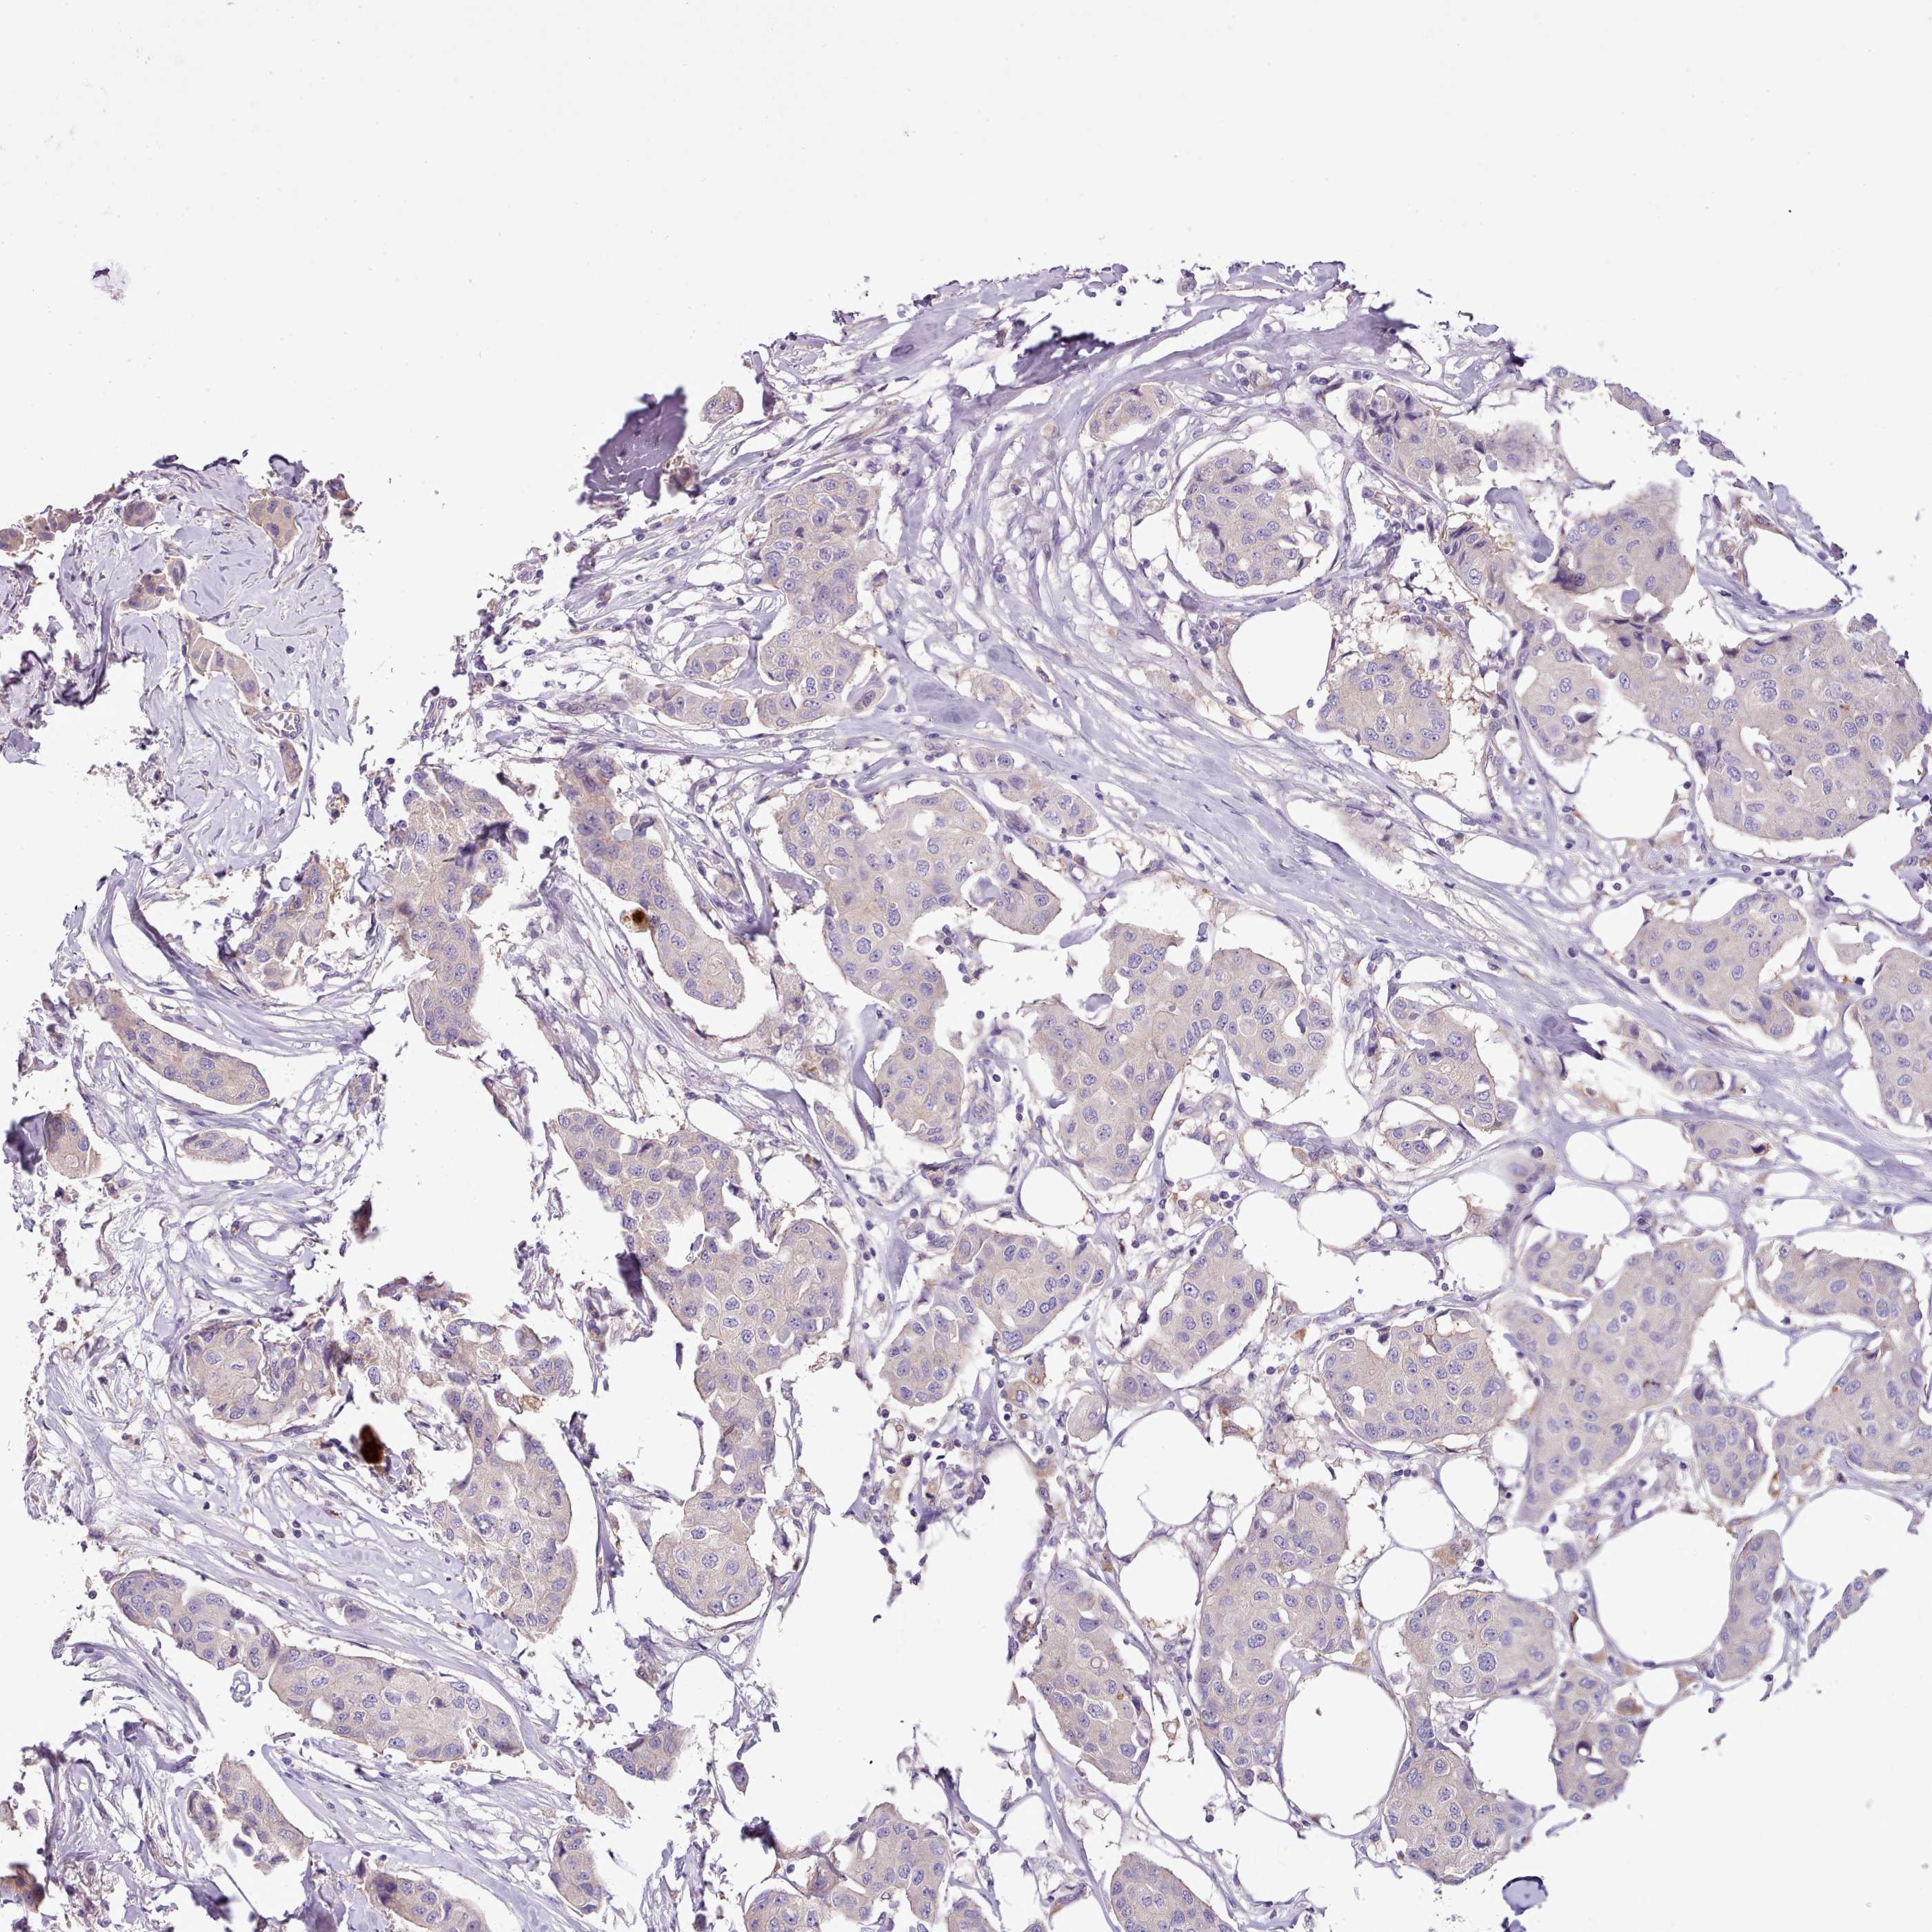

CANCER BREAST CANCER Show tissue menu

BRCA TCGA BRCA VALIDATION PROTEIN EXPRESSION